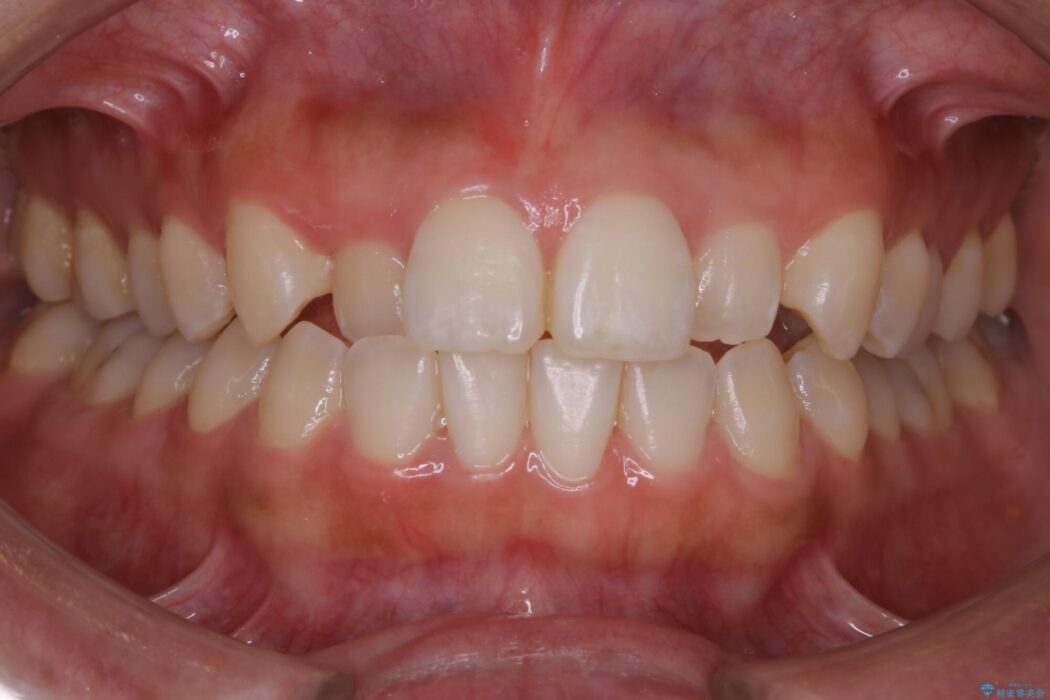

前歯の一部に反対咬合が見られ歯列がガタガタしていたためインビザラインでの矯正治療をご提案しました。

反対咬合の歯も整ったアーチに収まり、きれいに仕上がりました。

今回のケースでは前歯部の軽い凹凸のみであったため部分矯正の適応範囲に該当していました。